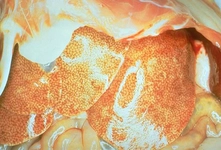

Karaciğer Parankim Dansitesi Neden Azalır?Karaciğer, vücutta metabolizmanın düzenlenmesi, toksinlerin temizlenmesi ve çeşitli biyolojik işlevlerin gerçekleştirilmesi açısından kritik öneme sahip bir organdır. Karaciğer parankimi, karaciğerin işlevsel dokusunu oluşturur ve bu dokunun dansitesi, karaciğerin sağlığı hakkında önemli bilgiler sunar. Parankim dansitesinin azalması, karaciğerin normal işlevini etkileyebilir ve çeşitli sağlık sorunlarına yol açabilir. Bu makalede, karaciğer parankim dansitesinin azalmasının nedenleri ve sonuçları üzerinde durulacaktır. 1. Karaciğer Parankim Dansitesi Nedir?Karaciğer parankim dansitesi, karaciğerin işlevsel dokusunun yoğunluğunu ifade eder. Normal sağlıklı bir karaciğerde, parankim hücreleri (hepatositler) düzenli bir yapı içinde bulunur ve bu hücrelerin yoğunluğu, karaciğerin işlevselliği açısından kritik öneme sahiptir. Parankim dansitesinin azalması, genellikle hücre kaybı, hücre dejenerasyonu veya anormal hücre büyümesi gibi durumları gösterebilir. 2. Karaciğer Parankim Dansitesinin Azalmasının NedenleriKaraciğer parankim dansitesinin azalmasına neden olan faktörler çeşitlilik göstermektedir. Bu faktörler arasında:

3. Karaciğer Parankim Dansitesinin Azalmasının SonuçlarıKaraciğer parankim dansitesinin azalması, çeşitli sağlık sorunlarına yol açabilir. Bu sonuçlar arasında: